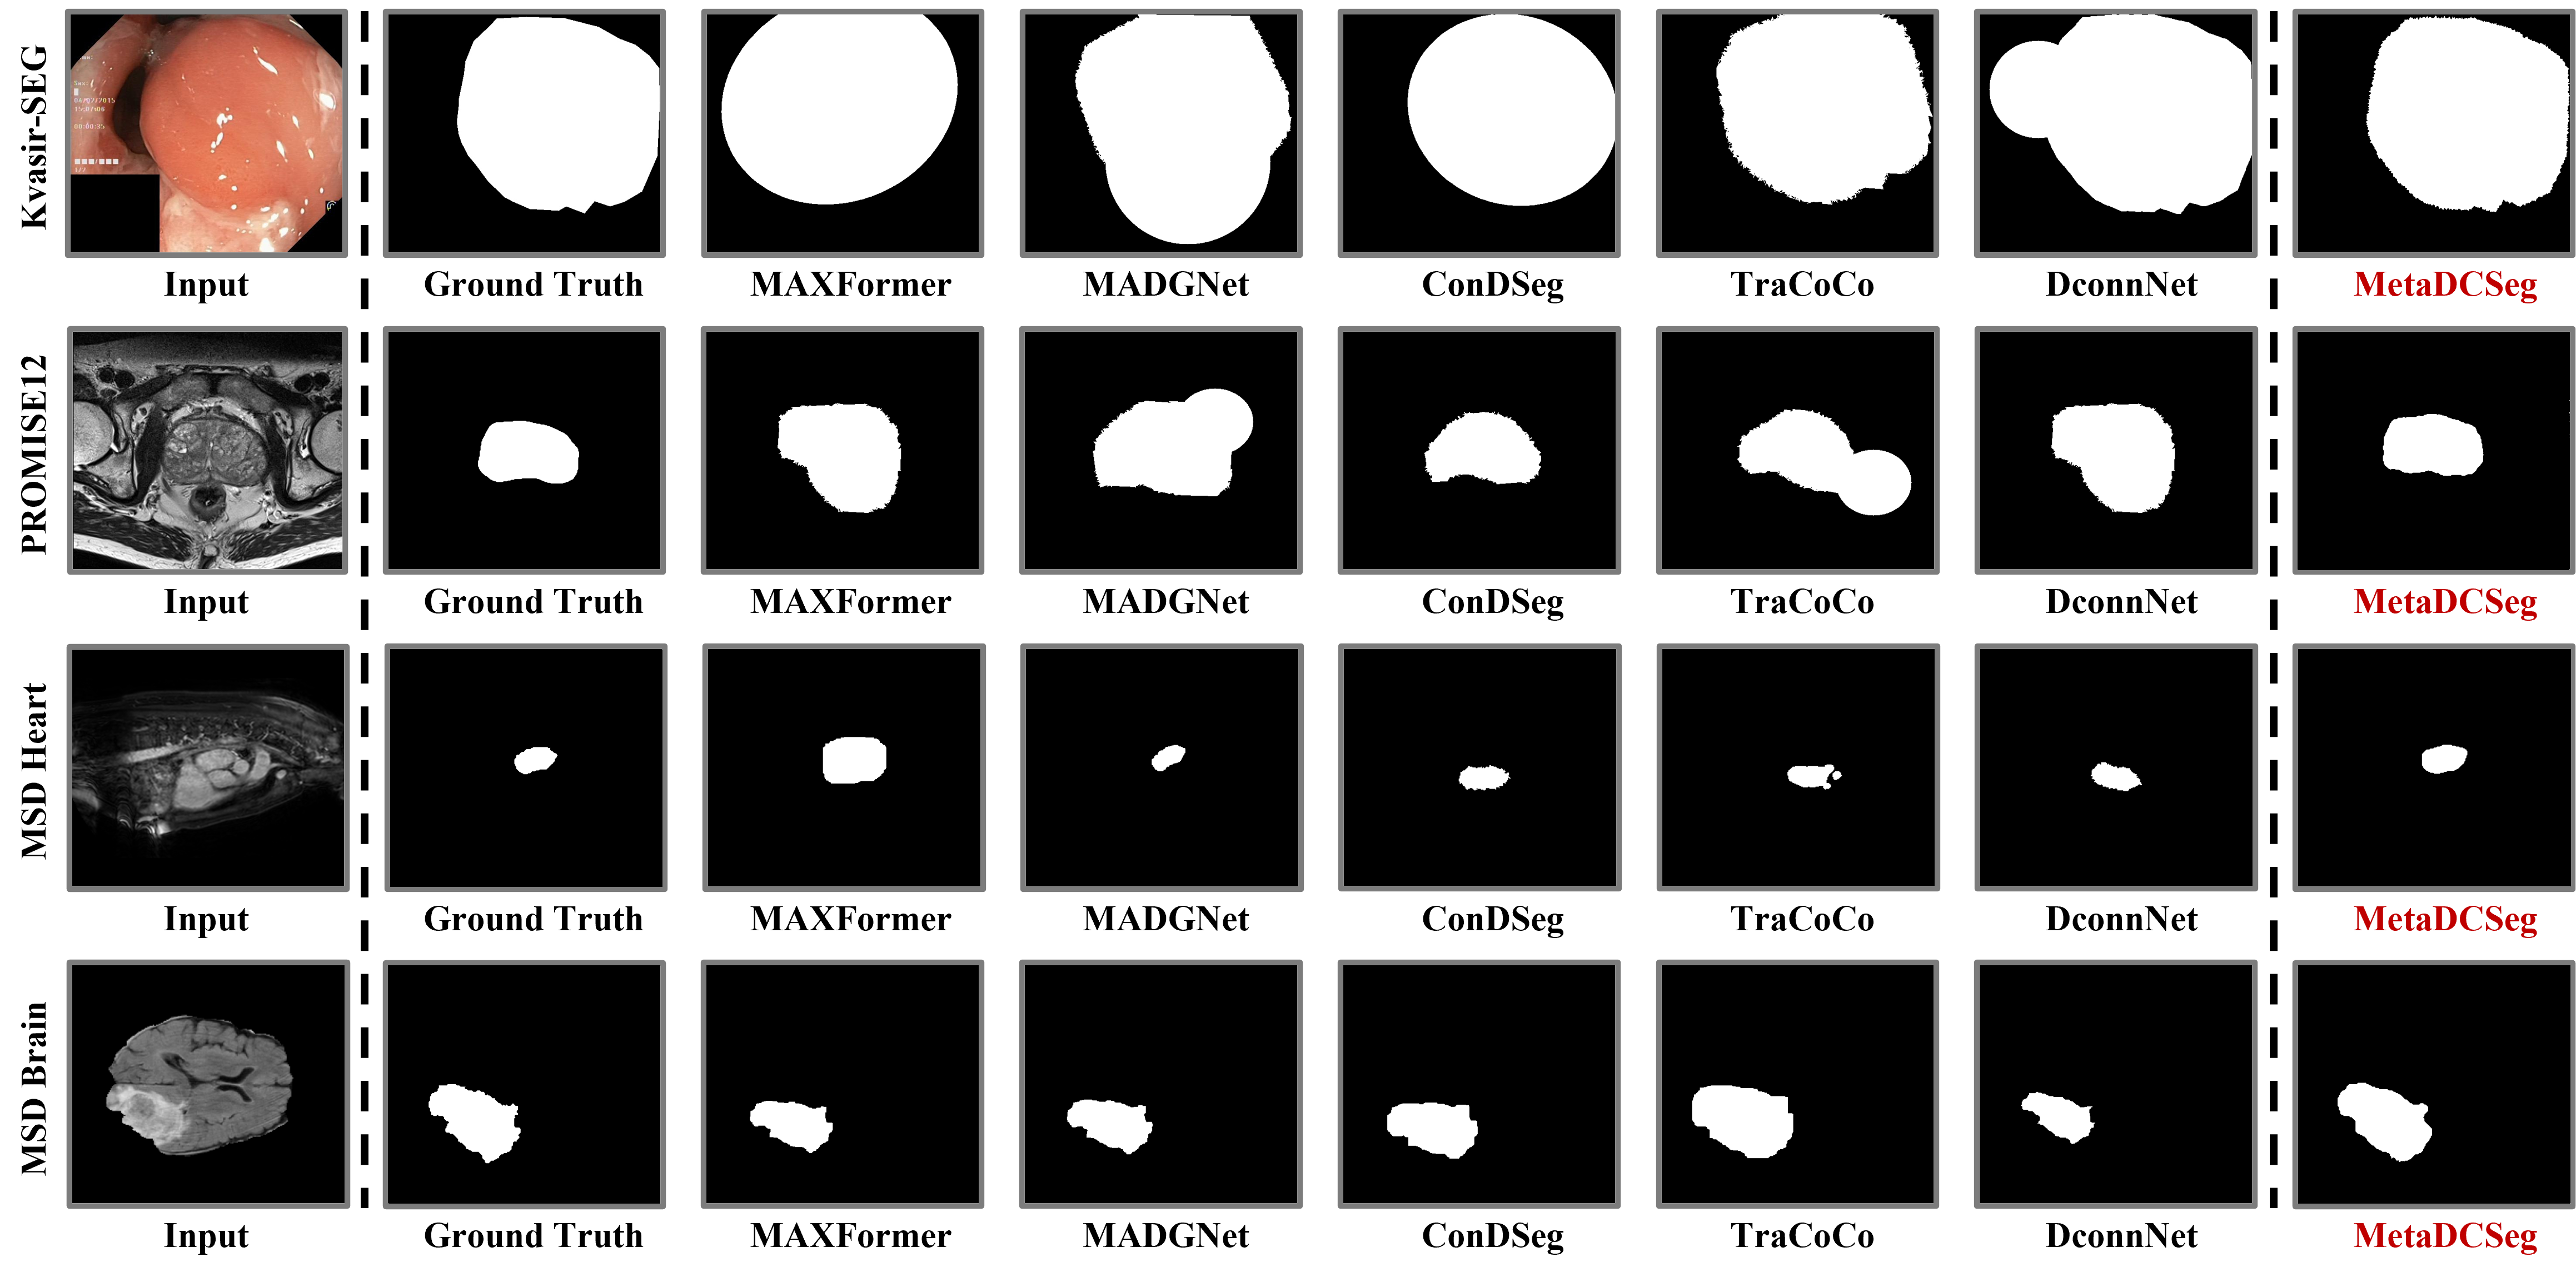

Refer to caption

Figure 4: Visual comparison of segmentation methods on Kvasir-SEG, PROMISE12, MSD Heart, and MSD Brain datasets.

We evaluate MetaDCSeg against five state-of-the-art methods across four medical segmentation datasets under clean conditions (0% noise) and noisy supervision (20%, 40%, and 60% noise levels). Importantly, as shown in Table 1, MetaDCSeg achieves 79.58% mIoU on clean MSD Heart data, surpassing L2B (Zhou et al., 2024) by 1.66%, demonstrating that our noise-handling components do not compromise performance on high-quality annotations. This trend continues across datasets: on Kvasir-SEG (Table 2), MetaDCSeg achieves 93.47% mIoU at 0% noise, improving 1.62% over L2B; on MSD Brain (Table 3), we achieve 77.82% mIoU, an 8.37% improvement over ConDSeg (Lei et al., 2025); and on PROMISE12 (Table 4), we reach 87.15% mIoU, surpassing HAMIL (Zhong et al., 2023) by 1.48%. These clean-data results validate that our meta-learning framework introduces minimal overhead when noise is absent. As noise increases, MetaDCSeg’s superiority becomes more pronounced: at 60% noise, we maintain 71.86% mIoU on MSD Heart (5.97% above L2B), 81.51% on Kvasir-SEG (8.68% above L2B), and remarkably 67.54% on MSD Brain where MAXFormer (Liang et al., 2023) catastrophically fails at 10.75%. On PROMISE12 at 60% noise, MetaDCSeg achieves 80.49% mIoU, a 13.96% improvement over HAMIL, while MADGNet (Nam et al., 2024) collapses to merely 4.10%. The consistent improvements from 0% to 60% noise demonstrate that MetaDCSeg not only excels under noisy supervision but also maintains competitive or superior performance on clean data, confirming our approach effectively adapts to varying annotation quality without sacrificing baseline accuracy.